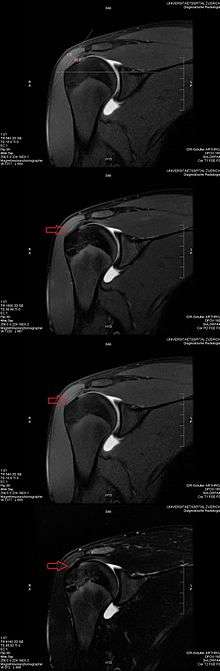

Application to medical imaging: The magic angle artifact

The magic angle artifact refers to the increased signal on sequences with short echo time (TE) (e.g., T1 or PD spin-echo sequences) in MR images seen in tissues with well-ordered collagen fibers in one direction (e.g., tendon or articular hyaline cartilage).[1] This artifact occurs when the angle such fibers make with the magnetic field is equal to θm.

Example: This artifact comes into play when evaluating the rotator cuff tendons of the shoulder. The magic angle effect can create the appearance of supraspinatus tendinitis.